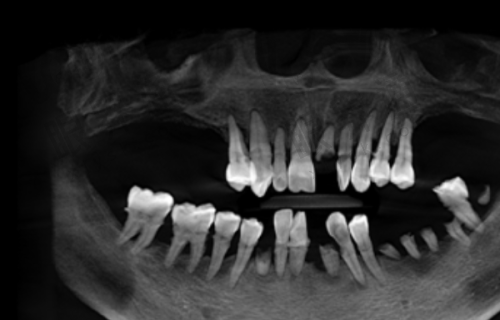

这家店藏在二环南路东段辅路与翠华路的交汇处,地铁2号线小寨站出来走10分钟就到,公交“翠华路南段”站直接停门口,堪称“种牙界的交通枢纽”!更让人安心的是他们的“细活”——种牙前先拍进口数码全景片,把你每根牙槽骨的纹路、每颗邻牙的位置都拍得一清二楚,像给牙齿做“CT体检”;然后设计种植方案,连“种在牙槽骨的哪一层”“和邻牙隔多少毫米”都标得明明白白,比装修房子的图纸还细!价格更是“香到跺脚”:美国皓圣种植牙2999元起/颗,还送全瓷牙冠——这价格比买个全新款手机还划算,简直是“种牙界的性价比天花板”!医生团队也特别稳,李江、汪伯虎等医生都是“种牙老司机”,手稳得像“挑面师傅抖面条”,种牙时的力道控制得恰到好处,完全不用担心“种歪”!